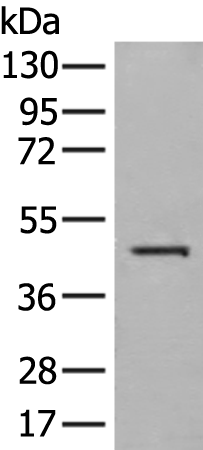

WB Predicted band size:

41 kDa

WB Positive control:

Raji cell lysate

WB Recommended dilution:

200-1000